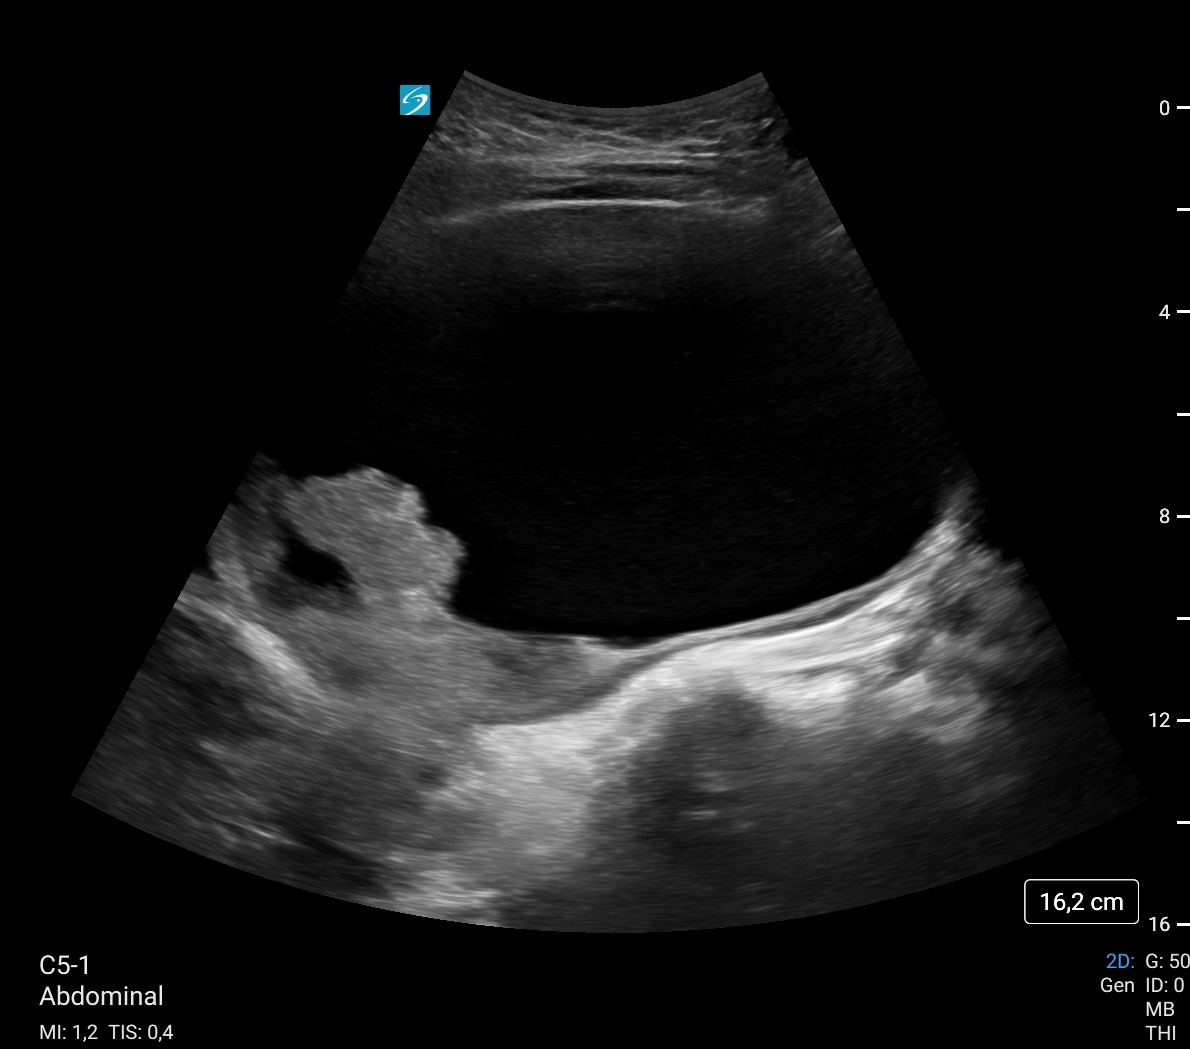

Ecografía a pie de cama: Vejiga 700 cc con imagen hiperecogénico intravesical, irregular, pensando en coágulo como primera opción sin poder descartar tm vesical. Sospecha de retención aguda de orina (RAO) con probables de coágulos intravesicales vs posible tumor vesical.

Vejiga urinaria a máxima repleción, identificando contenido hiperecoico de morfología tubular en pared lateral inferior izquierda, parece desplazarse a los meatos con los cambios posicionales, lo que sugiere existencia de coágulos como primera posibilidad, sin poder descartar tumor subyacente. Se recomienda valoración con cistoscopia, lavados vesicales...